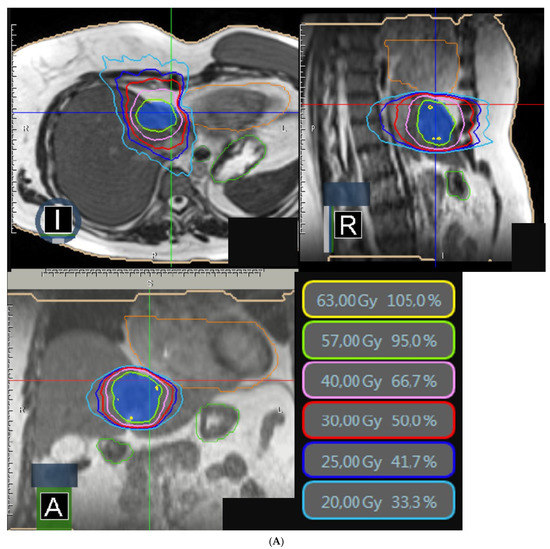

| PTV | |

| V95% (%) V100% (%) D95% (Gy) D1cc (Gy) | 95.9 (71.6–98.9) 50.0 (49.2–90.8) 47.5 (26.9–58.0) 52.0 (41.2–63.1)) |